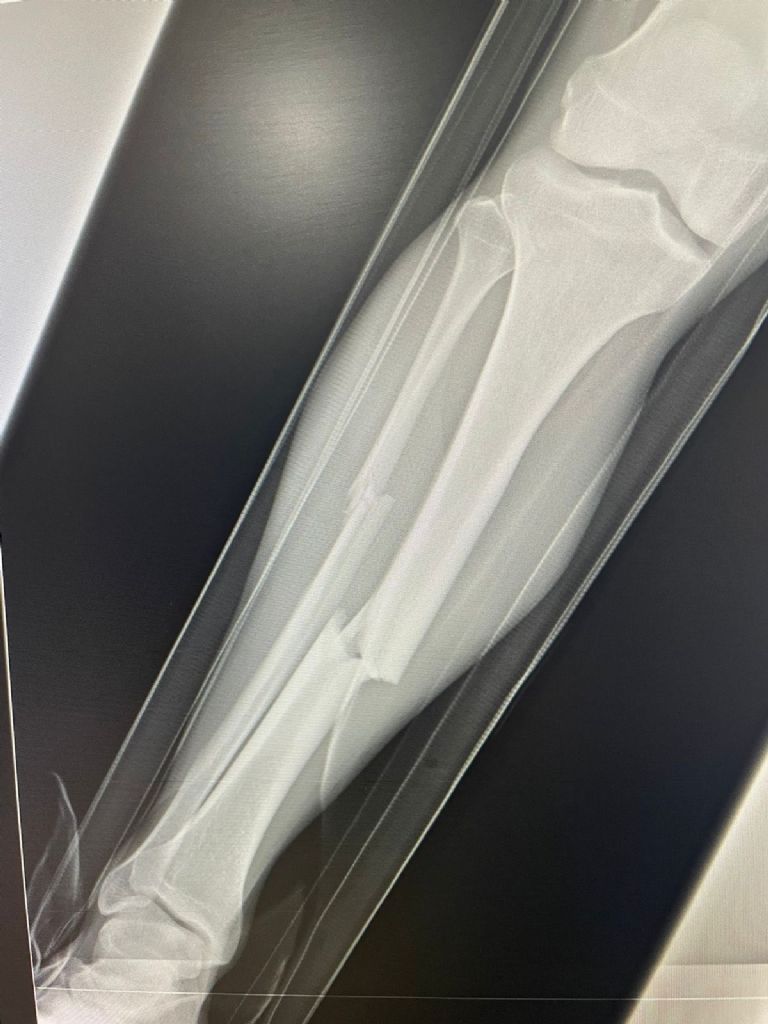

Por su parte, el club Atlante informó que el jugador fue trasladado de inmediato al hospital tras la agresión que sufrió por parte de Luis Ruiz. Detalló que tras una revisión realizada por el cuerpo médico del equipo, al Hobbit Bermúdez se le diagnosticó una fractura de tibia y peroné en la pierna derecha. Debido a la gravedad de la lesión, será sometido a un procedimiento quirúrgico, por lo que se perderá el resto de la temporada.

El Hobbit en una ambulancia del estadio ciudad de los deportes y fue trasladado al hospital donde se le tomaron algunas radiografías en las cuales se pudo observar el estado de su pierna derecha, la cual tenía una fractura expuesta. Hasta el momento, la Liga de expansión no ha informado sobre alguna sanción en contra de Ruiz. Además de la roja directa que le sacó el árbitro por la falta cometida.